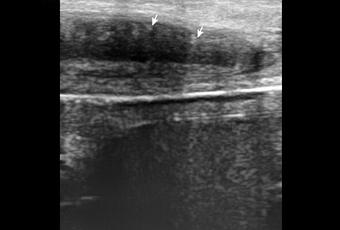

A nivel de base del pené, entre los cuerpos cavernoso y esponjoso en su porción central se observa la presencia de calcificación, que mide 2.2 mm. En tercio distal del pené, a nivel de cuerpos cavernosos con presencia de calcificación que mide 1.8 mm.

A NIVEL DE BASE Y TERCIO DISTAL DEL PENÉ, EN CUERPOS CAVERNOSOS CON PLACAS A RELACIÓN A ENFERMEDAD PEYRONIE.